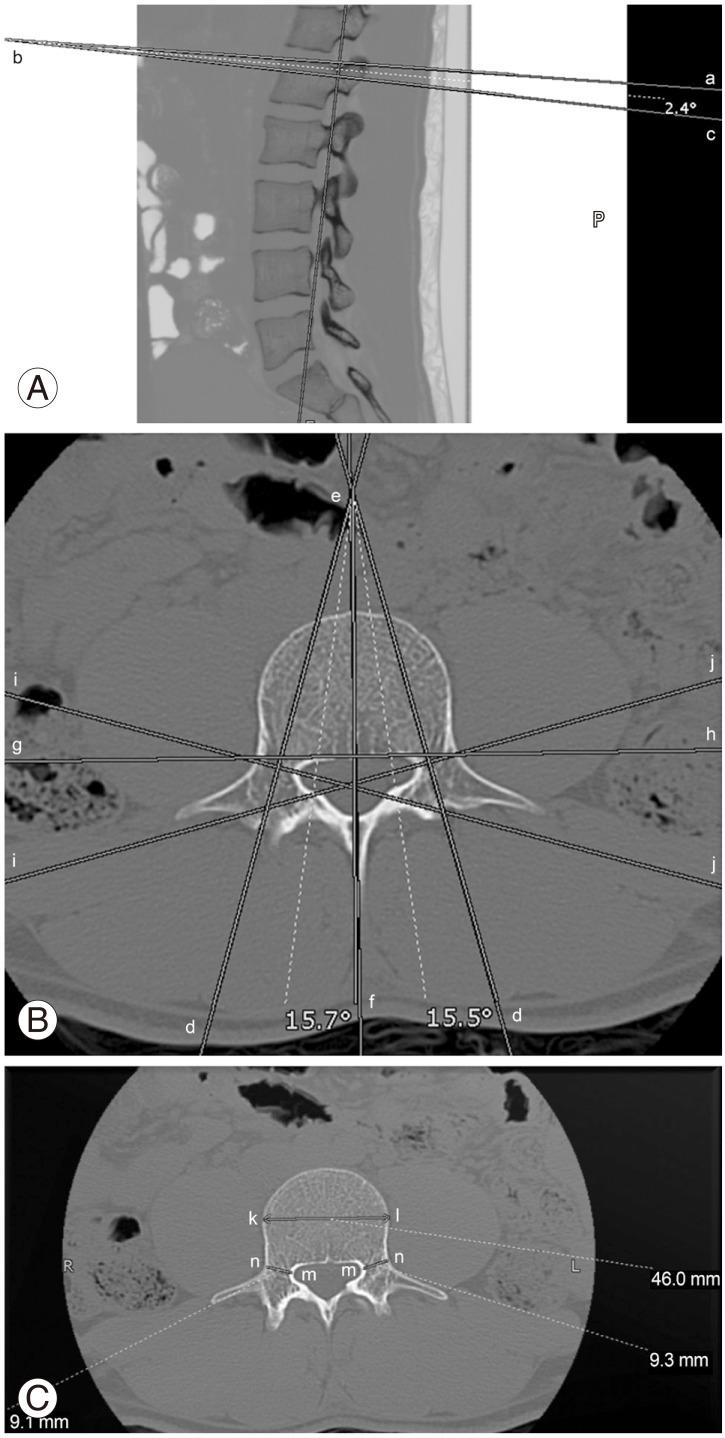

An observational study was conducted based on a review of thin-cut (3 mm) computed topographic images of lumbar vertebrae. Two-hundred and twenty vertebrae from forty-nine patients were studied, and various dimensions were analyzed.

Generally, the size of the vertebrae, vertebral canals and recesses were found to be greater in male patients. The difference was statistically significant for transverse and anteroposterior diameters of the vertebral bodies and sagittal diameter of pedicles on the left side (p<0.05). Comparison of populations revealed statistically significant differences in pedicle dimensions between Pakistani population and others.